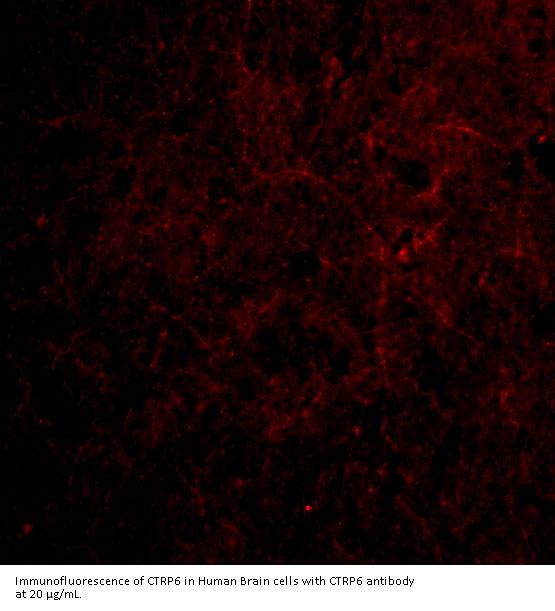

CTRP6 antibody can be used for the detection of CTRP6 by Western blot at 0.5 - 2 μ g/mL. Antibody can also be used for immunohistochemistry starting at 10 μ g/mL. For immunofluorescence start at 20 μ g/mL.

Antibody validated: Western Blot in mouse samples; Immunohistochemistry in human samples and Immunofluorescence in human samples. All other applications and species not yet tested.